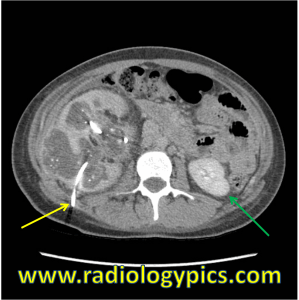

Xanthogranulomatous Pyelonephritis - Axial CT of the abdomen at the level of the kidneys shows a right sided percutaneous nephrostomy tube (yellow arrow) which has been placed to drain the chronically obstructed right kidney. The normal left kidney is indicated by the green arrow.

Xanthogranulomatous Pyelonephritis – Axial CT of the abdomen at the level of the kidneys shows a right sided percutaneous nephrostomy tube (yellow arrow) which has been placed to drain the chronically obstructed and infected right kidney. The normal left kidney is indicated by the green arrow.

This is a case of xanthogranulomatous pyelonephritis, which is defined as a chronic infection of the kidney and surrounding structures, destruction of renal parenchyma, and infiltration with lipid-laden macrophages. It is the lipid-laden macrophages which characteristically give this entity its name “xanthogranulomatous.” Xanthos is the Greek word for yellow, which this entity looks like on gross specimens in the pathology lab. Xanthogranulomatous pyelonephritis is usually associated with large staghorn calculi and is difficult to distinguish from other neoplasms such as renal cell carcinoma.